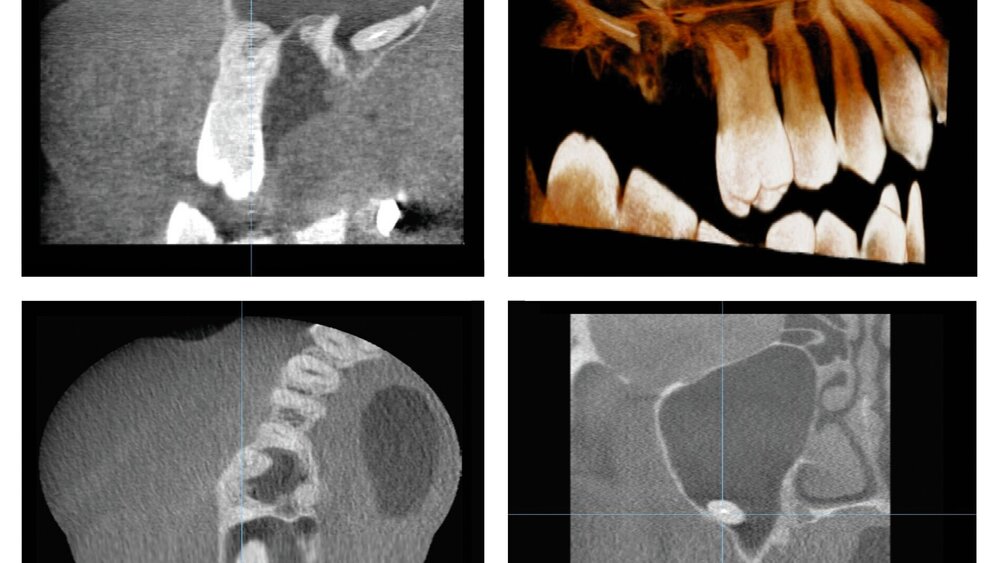

Eine Leitlinie aus dem Bereich der Röntgendiagnostik behandelt notwendigerweise immer wichtige Strahlenschutz-Aspekte, da hier Empfehlungen für den sinnvollen Gebrauch von potenziell schädlicher ionisierender Strahlung formuliert werden. Der Strahlenschutz in der zahnmedizinischen Röntgenbildgebung hat seit der Einführung der DVT fundamental an Bedeutung gewonnen, da diese dreidimensionale Röntgentechnik im Vergleich zum zweidimensionalen Röntgen (intraorale Tubus-, Fernröntgen- und Panoramaschichtaufnahmen) eine substanziell höhere Dosis mit sich bringt [Ludlow et al., 2015; IAEA, 2022].

Dies hat sich trotz der Einführung Dosis-sparender Protokolle nicht wesentlich geändert, so dass zunehmende Bedenken hinsichtlich der Strahlenrisiken geäußert werden [White et al., 2014]. Zwar kann durch Optimierung eine deutliche Dosisreduktion erfolgen bei gleichzeitig immer noch diagnostizierbaren Bildern [Oenning et al., 2019], doch bleibt im Moment sehr fraglich, wie häufig derartig optimierte Protokolle in der täglichen Anwendung wirklich eingesetzt werden.

Interessant ist auch die Einschränkung der Indikation für eine DVT-Aufnahme bei den unteren Weisheitszähnen. Die entsprechende Empfehlung stellt fest, dass eine „dreidimensionale Bildgebung [...] vor einer Weisheitszahnentfernung nicht erforderlich [ist], wenn in der konventionell zweidimensionalen Bildgebung keine Hinweise auf eine besondere Risikosituation vorliegen“ (Konsens). Diese Einschränkung spiegelt die für diese Fragestellung mittlerweile recht eindeutige Literaturlage wider. Zudem werden Weisheitszähne zu einem Großteil bei einer jungen (unter 25 Jahre alten) und damit besonders strahlenempfindlichen Bevölkerungsgruppe entfernt.

Neu ist eine Empfehlung zur Kieferhöhlendiagnostik, wo bei klinischem Verdacht auf eine odontogene Sinusitis zur Ursachenabklärung eine intraorale Tubus- oder eine Panoramaschichtaufnahme angefertigt werden sollte — nur bei „erweitertem bilddiagnostischem Abklärungsbedarf der Kieferhöhlen sollte eine Schnittbilddiagnostik mit einem DVT oder CT erfolgen".

Generell zeigt die Leitlinie, dass die DVT nicht als routinemäßig einzusetzende Methode der Bildgebung angewendet werden sollte. Sie sollte überwiegend erst zum Zuge kommen, wenn die zweidimensionale Bildgebung und/oder auch die klinische Untersuchung therapeutisch relevante Fragestellungen nicht beantworten können oder eine besondere Risikosituation vorliegt, die durch eine 3-D-Bildgebung besser bewertet werden kann.